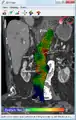

Biomechanical AAA rupture risk prediction

An aneurysm ruptures if the mechanical stress (tension per area) exceeds the local wall strength; consequently, peak wall stress (PWS),[30] mean wall stress (MWS),[31] and peak wall rupture risk (PWRR)[32] have been found to be more reliable parameters than diameter to assess AAA rupture risk. Medical software allows computing these rupture risk indices from standard clinical CT data and provides a patient-specific AAA rupture risk diagnosis.[33][34][35] This type of biomechanical approach has been shown to accurately predict the location of AAA rupture.[34][35][36]